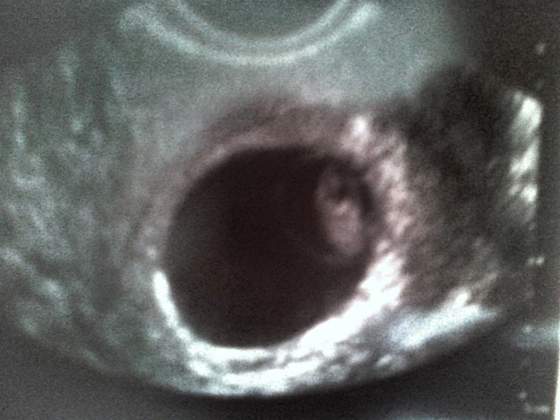

Ja również chciałam się przywitać :-) Do tej pory siedziałam cicho, żeby nie zapeszyć. Ale w środę 26 września byłam u lekarza, był to wtedy 6w6d, byłam przekonana, że nic nie zobaczę. Na pierwszej wizycie dwa tygodnie wcześniej był tylko pęcherzyk, więc starałam się podchodzić do tego w miarę spokojnie, chociaż wiadomo, że to i tak się nie udajeNo i był/a!!!

) prawie 9 mm i serducho biło jak szalone! baarrrrdzo wzruszający moment

Serce pięknie biło, równiutko i mocno!